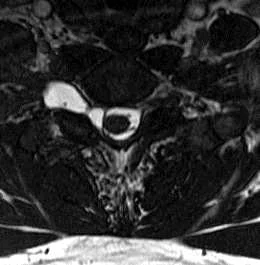

這題的解題核心在於辨識頸椎磁振造影(MRI)影像中的假性脊髓膜膨出(pseudomeningocele),並理解臂神經叢根部撕脫傷(root avulsion)的正確定義。圖片中右側明顯可見一個高訊號的囊狀結構,這就是典型的假性脊髓膜膨出,強烈暗示神經根撕脫傷。